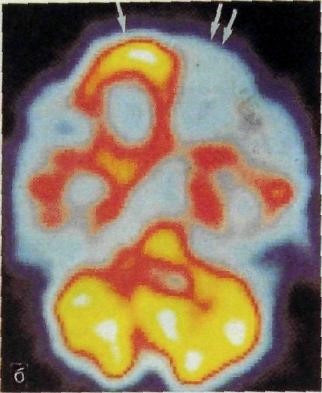

Исследование мозга методами радиоиуклидной диагностики ограничива­ется в основном получением функциональных данных. Принято считать, что величина мозгового кровотока пропорциональна метаболической ак­тивности головного мозга, поэтому, применив соответствующий РФП, на­пример пертехнетат, можно выявить участки гипо- и гиперфункции (рис. 44).

Рис. 44.   Эмиссионная  однофотонная томография головного мозга до (а) и после (б) эпилептического припадка. Снижение функциональной активности в лобной доле слева.

Такие исследования проводят для локализации эпилептических очагов, при выявлении ишемии у пациентов с деменцией, а также для изу­чения ряда физиологических функций головного мозга. В качестве метода радиоиуклидной визуализации, помимо сцинтиграфии, с успехом применя­ют однофотонную эмиссионную томографию и особенно позитронную эмиссионную томографию.          Последняя по техническим и экономическим соображениям, как отмечалось ранее, может быть выполнена только в крупных научных центрах.